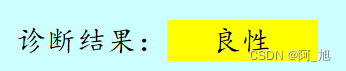

诊断结果区域:分别用'绿色'、‘黄色’、‘红色’背景代表‘正常’、‘良性’、‘恶性’这3种类别的检测结果。

显示效果如下: